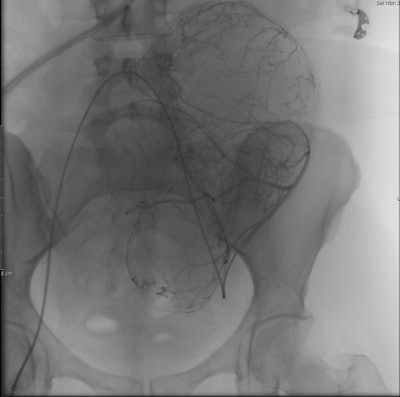

خلال عملية معالجة الورم الليفي الرحمي بالقثطرة.

تتميز معالجة الأورام الليفية الرحمية عن طريق القثطرة بأنها أبسط و بأن نسبة المشاكل والاختلاطات أقل مقارنة بالاستئصال الجراحي حيث يتم اجراء القسطرة بدون تخدير عام و ياخذ الاجراء 45 دقيقة و تخرج المريضة من المشفى في نفس اليوم.

الأدوات التي تستخدم عادة في علاج الأورام الليفية الرحمية بالقثطرة:Robert catheter, microcatheter, and embolization particles.